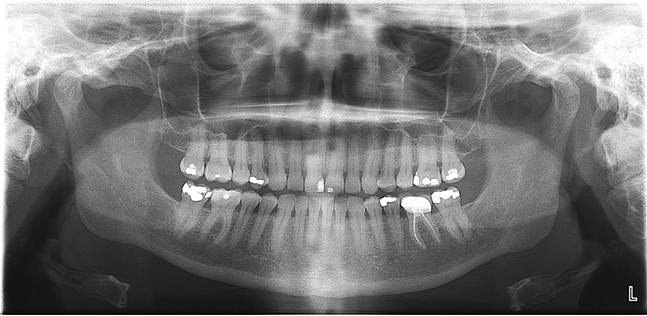

(2.) Panoramic radiographs are options when intraoral radiography is impractical or additional diagnostic information is required.

Figure 2

Panoramic

A digital panoramic radiograph (Figure 2) is indicated for circumstances in which intraoral imaging is not practical, as in patients who cannot open their mouths due to trismus or in those who cannot tolerate having a sensor or film in their mouth due to severe mucositis following radiation therapy for cancer. Advantages of panoramic imaging are that it quickly provides broad coverage of facial bones and teeth, it is convenient for both dental practitioner and patient, and is a helpful visual aid in patient education and case presentation.

Drawbacks of panoramic imaging are the cost—$25,000 to $85,00019—and that vertical beam angulation is not adjustable. Also, like a traditional panoramic machine, the digital unit requires dedicated operatory space, so there’s no space savings other than not needing a darkroom.